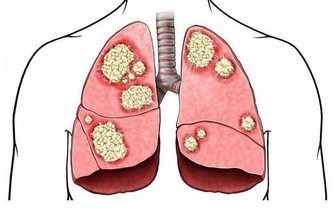

另外, 一些細菌或已入侵傷口內, 那時便需要多些血液中的白血球,巨噬細胞去抵抗細菌及病原體.

由於以上兩個過程也需要血液提供,組織損傷後會釋出一種化學物質,叫做組織胺,

它可刺激微血管,使其擴張,血流量增加;還使血管壁的通透性增大,

使血液中一些成分漏出,也使血液中的白血球更容易溢出。

成為炎性反應- 表現是局部的紅、腫、熱、痛現象。